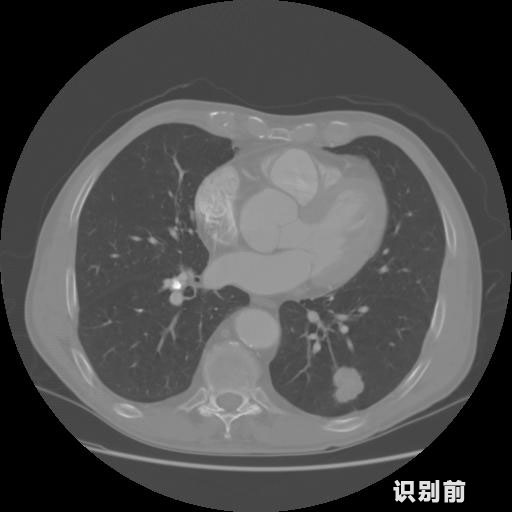

英特健康A(chǔ)I深度學(xué)習(xí)醫(yī)療圖像識別系統(tǒng)案例_胸部CT

03.jpg

報告:

1.發(fā)現(xiàn)肺結(jié)節(jié)的可能性為95.56%---位于框指數(shù)位置:[331.70554 366.13406 365.21707 403.96234]